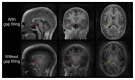

Magnetic Resonance Imaging (MRI) scanners produce loud acoustic noise originating from vibrational Lorentz forces induced by rapidly changing currents in the magnetic field gradient coils. Using zero echo time (ZTE) MRI pulse sequences, gradient switching can be reduced to a minimum, which enables near silent operation.Besides silent MRI, ZTE offers further interesting characteristics, including a nominal echo time of TE = 0 (thus capturing short-lived signals from MR tissues which are otherwise MR-invisible), 3D radial sampling (providing motion robustness), and ultra-short repetition times (providing fast and efficient scanning).In this work we describe the main concepts behind ZTE imaging with a focus on conceptual understanding of the imaging sequences, relevant acquisition parameters, commonly observed image artefacts, and image contrasts. We will further describe a range of methods for anatomical and functional neuroimaging, together with recommendations for successful implementation.